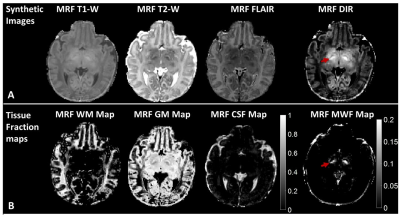

Figure 2: Synthetic MR images (A) and sub-voxel tissue fraction maps (B) generated from a subject (pt2, 15 days). The myelinated posterior limb of internal capsule is best defined on the DIR and MWF images (arrowed) and not visualized on the white matter fraction maps.